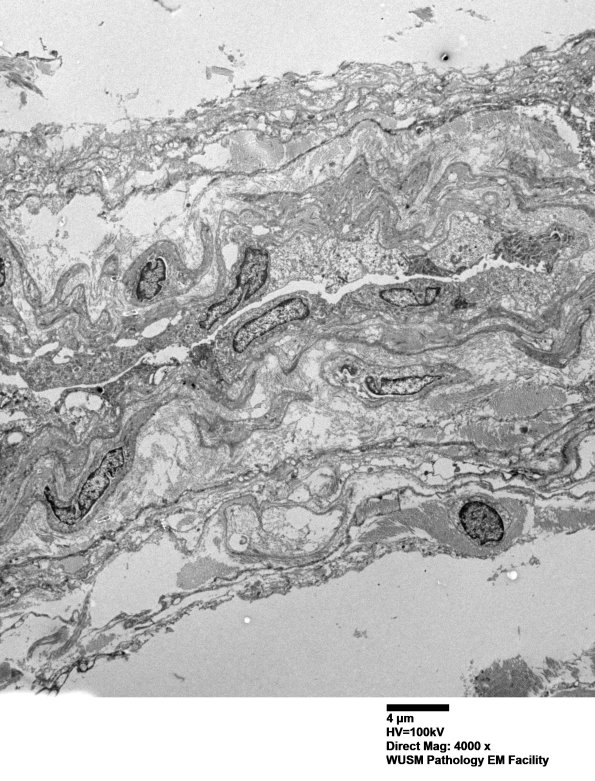

25J1,2 The ultrastructural appearance of the perineurium consisted of lamellar cells and their processes with basal laminae (arrow, 25J2). There were no axons within the hyperplastic perineurium. (electron micrographs)